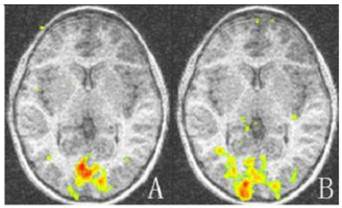

For the control group, there was no statistically significant difference between the striate and extrastriate cortical activation of the two eyes (t = -0.704, -0.896; P = 0.499, 0.394; Table 2, Fig. 2).

Figure 2

Representative cortex activation relative to baseline of both eyes of the control group. There is no significant difference in activation between the two eyes (P > 0.05). A: Cortex activation of left eye; B: Cortex activation of right eye. Areas with high and low activation are indicated by red and green colors.